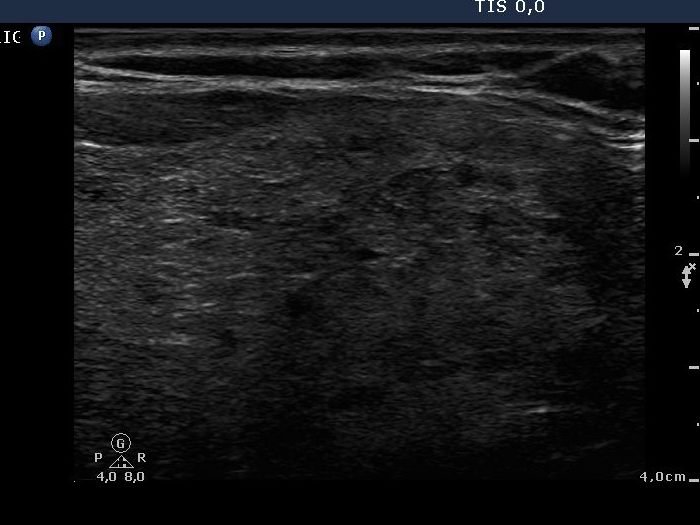

Benign Hashimoto's thyroiditis (cytological diagnosis) - case 1652

First, we demonstrate two cases of Hashimoto's thyroiditis with pronounced fibrotic changes. Both present pale and bright hyperechogenic granules and lines corresponding to normal and excessive connective tissue. Neither of the discrete areas are nodules in a pathological sense.